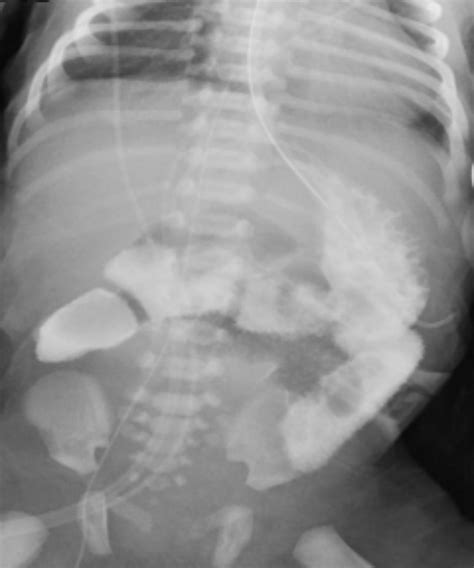

Diagnostic Imaging and the Ligament of Treitz

Radiologists rely on the Ligament of Treitz when interpreting imaging studies such as CT scans or fluoroscopy (barium swallow/meal). The position of the duodenojejunal flexure in relation to the vertebral column and the midline can provide diagnostic clues for anatomical anomalies. For instance, in a normal anatomical presentation, the flexure should be to the left of the midline and at the level of the L1 or L2 vertebrae.

When imaging confirms that the flexure is located to the right of the midline, it is a hallmark sign of intestinal malrotation. Recognizing these signs early through imaging can prevent life-threatening complications, especially in pediatric patients who are born with congenital intestinal positioning issues.